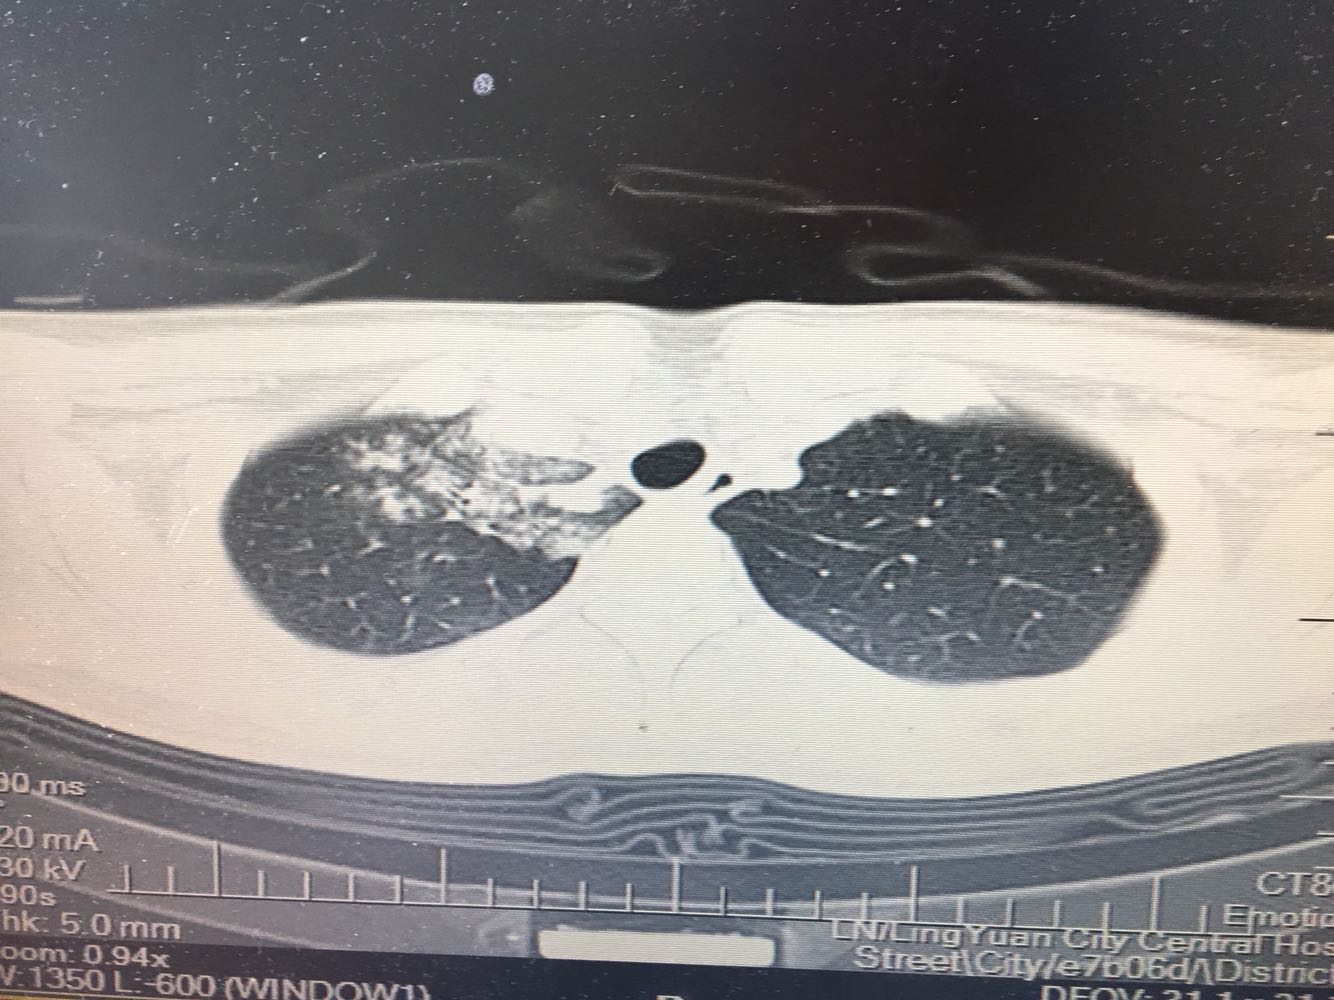

女,26岁,咳嗽1周,咳痰不畅,咽喉痒,口服阿莫西林无好转,昨日发热,体温38.5摄氏度,于门诊查肺CT后以肺炎收入院,病来无盗汗,无咳血,无消瘦及乏力,无头痛,无肢体酸痛,饮食睡眠可,二便正常

神清言明,咽部无充血,扁桃体不大,双肺呼吸音清,无罗音,服软无压痛。

支原体肺炎?肺结核?

支原体抗体1:160,结核抗体弱阳性。支原体肺炎个别可见上叶病变,该患无结核中毒症状,考虑支原体肺炎可能性大,但肺尖为结核好发部位,需要抗炎治疗后复查观察疗效。